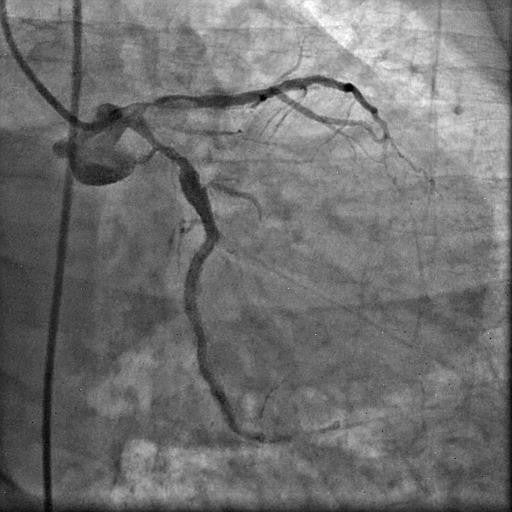

Picture 3: Diagnostic left coronary angiogram showing short, bifurcating left main (LM) with heavily calcified LAD and LCx with patent previously placed stents. There was significant ostio-proximal disease in both the LAD and LCx, along with total proximal occlusion of the OM branch.

Coronary angiography revealed a short, bifurcating left main (LM) with heavily calcified LAD, and LCx with patent previously placed stents.

There was significant ostio-proximal disease in both the LAD and LCx, along with total proximal occlusion of the OM branch. Right coronary angiography demonstrated a dominant vessel with extensive calcification and significant stenotic disease involving the proximal, mid, and distal segments.